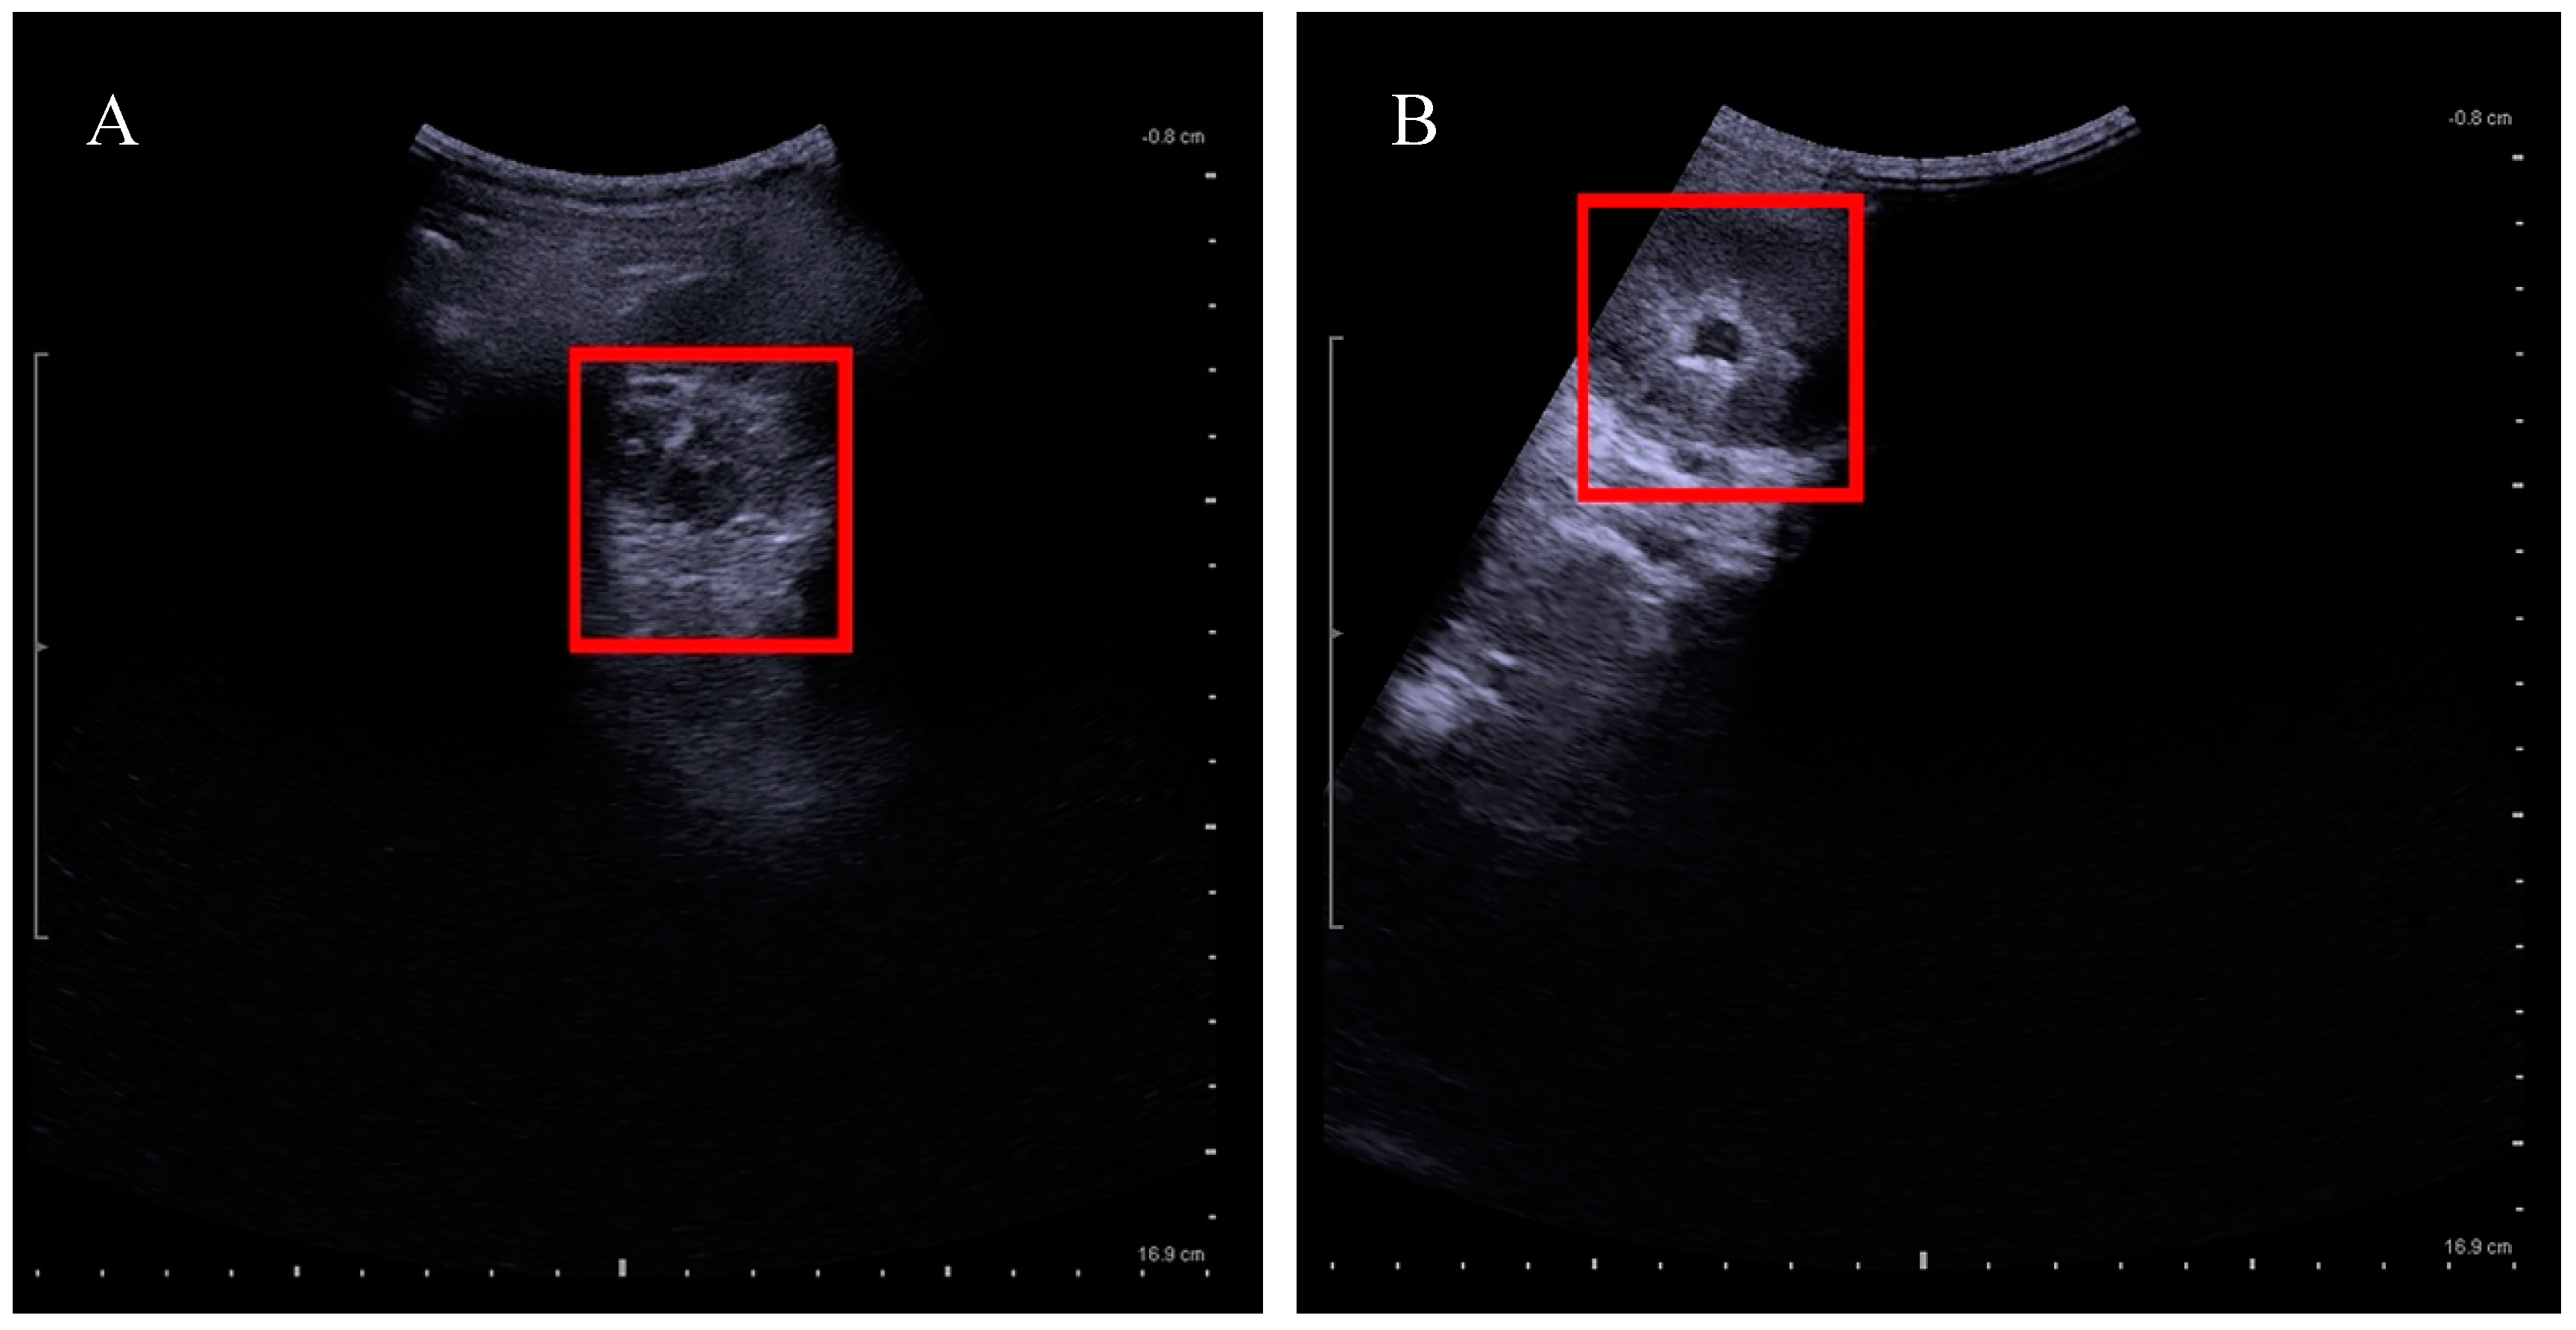

- KUB ultrasound has to be performed one month before and after the untethering surgery. Follow-up appointments are between three and six months depending on urological management